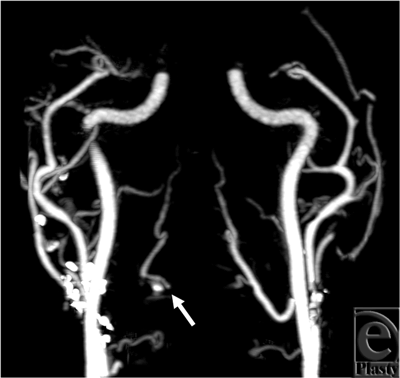

The cine loop (see Movie 1 [Click Here for Video]) demonstrates filling of the right lingual artery slightly after the filling of the left side, indicating retrograde flow from the contralateral circulation. On the static image, the proximal right lingual artery is not visualized; only distal portions of the artery fill with contrast, making it difficult to determine whether there is a joint facial-lingual segment that branches from the external carotid artery, or rather that this vessel fills in a retrograde fashion (Fig 1). Other major arterial findings are consistent between cine and static image analyses.

![]() |

| Figure 1. Best arterial phase from subject 1. The right lingual artery is illustrated in only distal parts (arrow). |